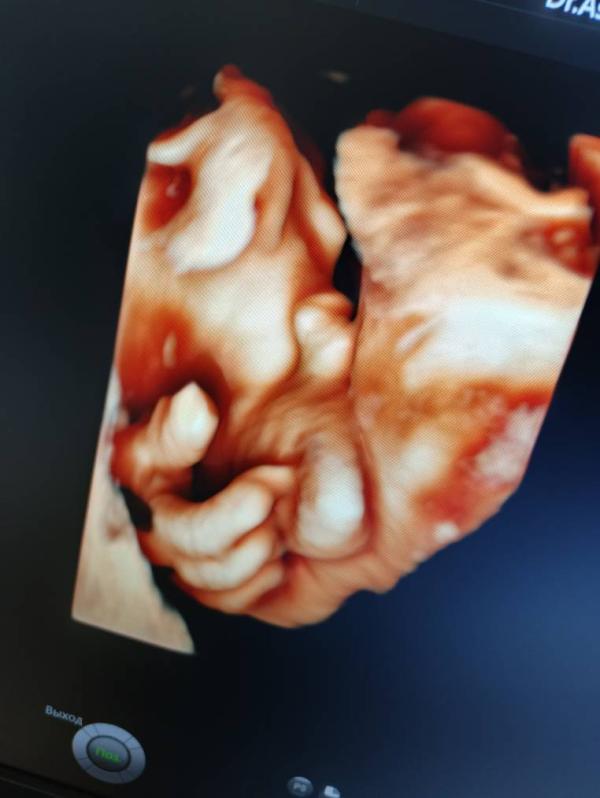

🫣 для тех, кто до сих пор считает , что узи с полом может ошибаться всю беременность.

Ошибка на первом скрининге вполне возможна. Ну, или если есть аномалия половых органов.

Кажется, чешет я...🤣